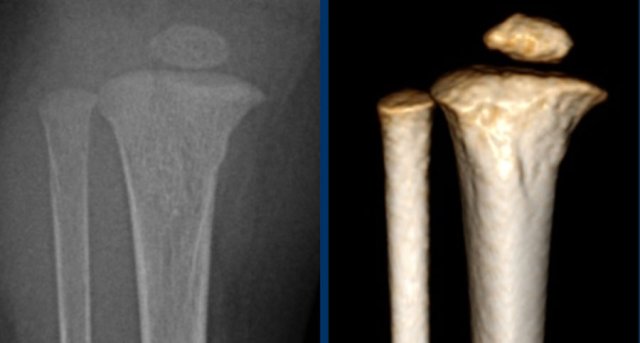

Brain CT in suspected abuse

CT of the brain should be performed on all suspected abuse victims under one year old.

Children who are older than one year and have external evidence of head trauma and/or abnormal neurological symptoms or signs should also have a CT scan of the head.

A CT scan is superior in detecting skull fractures (especially 3D reconstructions) and demonstrates subdural haemorrhages (ref).

Image

The x-rays show a rare case

of spondylometaphyseal dysplasia corner fracture type.

In these

children the form of the metaphysis is irregular resembling an old corner

fracture. However, vertebral anomalies are also present.